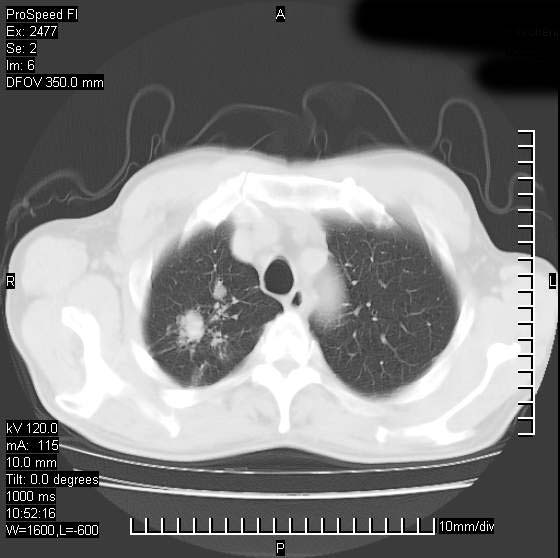

以下是引用天南地北在2007-10-9 14:29:00的发言:[br]1:右上肺结核[br]2:右肺下叶肿块:不支持肺癌,首先考虑炎性病变-肺脓疡可能性大[br]理由:1:临床病史支持,肺脓肿症状不明显应该是不规则服药造成。[br] 2:肿块边缘模糊,周围可见炎性渗出,长毛刺,内见支气管征,不过有点不规则。[br] 我感觉下肺癌这个诊断有点偏左,建议积极抗炎治疗后复查

以下是引用卜一在2007-10-9 15:55:00的发言:[br][br] [br] 1:右上肺结核[br]2:右肺下叶肿块:不支持肺癌,首先考虑炎性病变-肺脓疡可能性大[br]理由:1:临床病史支持,肺脓肿症状不明显应该是不规则服药造成。[br] 2:肿块边缘模糊,周围可见炎性渗出,长毛刺,内见空气支气管征,不过有点不规则。[br] 我感觉下肺癌这个诊断有点偏左,建议积极抗炎治疗后复查![br]支持! [br] [br] [br]

以下是引用wxy7406在2007-10-9 21:02:00的发言:[br]结合临床病史首先考虑感染性病变,但周围型肺癌不能除外,1.患者年龄偏大2.临床有咯血3.(也觉得是最重要的一点)病灶内有偏心性空洞。

以下是引用王仕学在2007-10-9 13:48:00的发言:[br]右下肺周围性肺癌可能性大,最好活检吧

以下是引用hhcckk在2007-10-9 15:18:00的发言:[br]右上肺病灶考虑结核,病灶多种形态并存(纤维化、增殖性病灶并存)[br]右下肺病灶比较难说,个人意见更趋向于“天南地北”的诊断----肺脓肿[br]1、病人有明显的寒战,高热,肿瘤病人很少出现[br]2、病灶周围的肺纹理走向柔和,没有肿瘤病灶常见的集束征[br]3、病灶边缘的毛刺较长,恶性肿瘤多为短毛刺[br]痰中血丝和病人的年龄是两个不利于良性肿块的因素,建议早点活检

以下是引用ydx_74在2007-10-9 15:53:00的发言:[br]右上肺结核,右下中心性肺癌可能大,肺门淋巴结肿大。